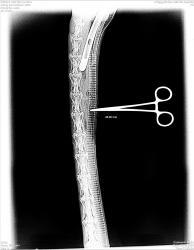

Желательно представление изображений, полученных при использовании данной системы.

Спасибо за представленные изображения.

Еще раз спасибо за представленные изображения, но на изображении кисти и лучезапястного сустава в прямой проекции создается впечатление, что "снимок недобит" - мягкий, и по качеству "проигрывает рентгенограмме".